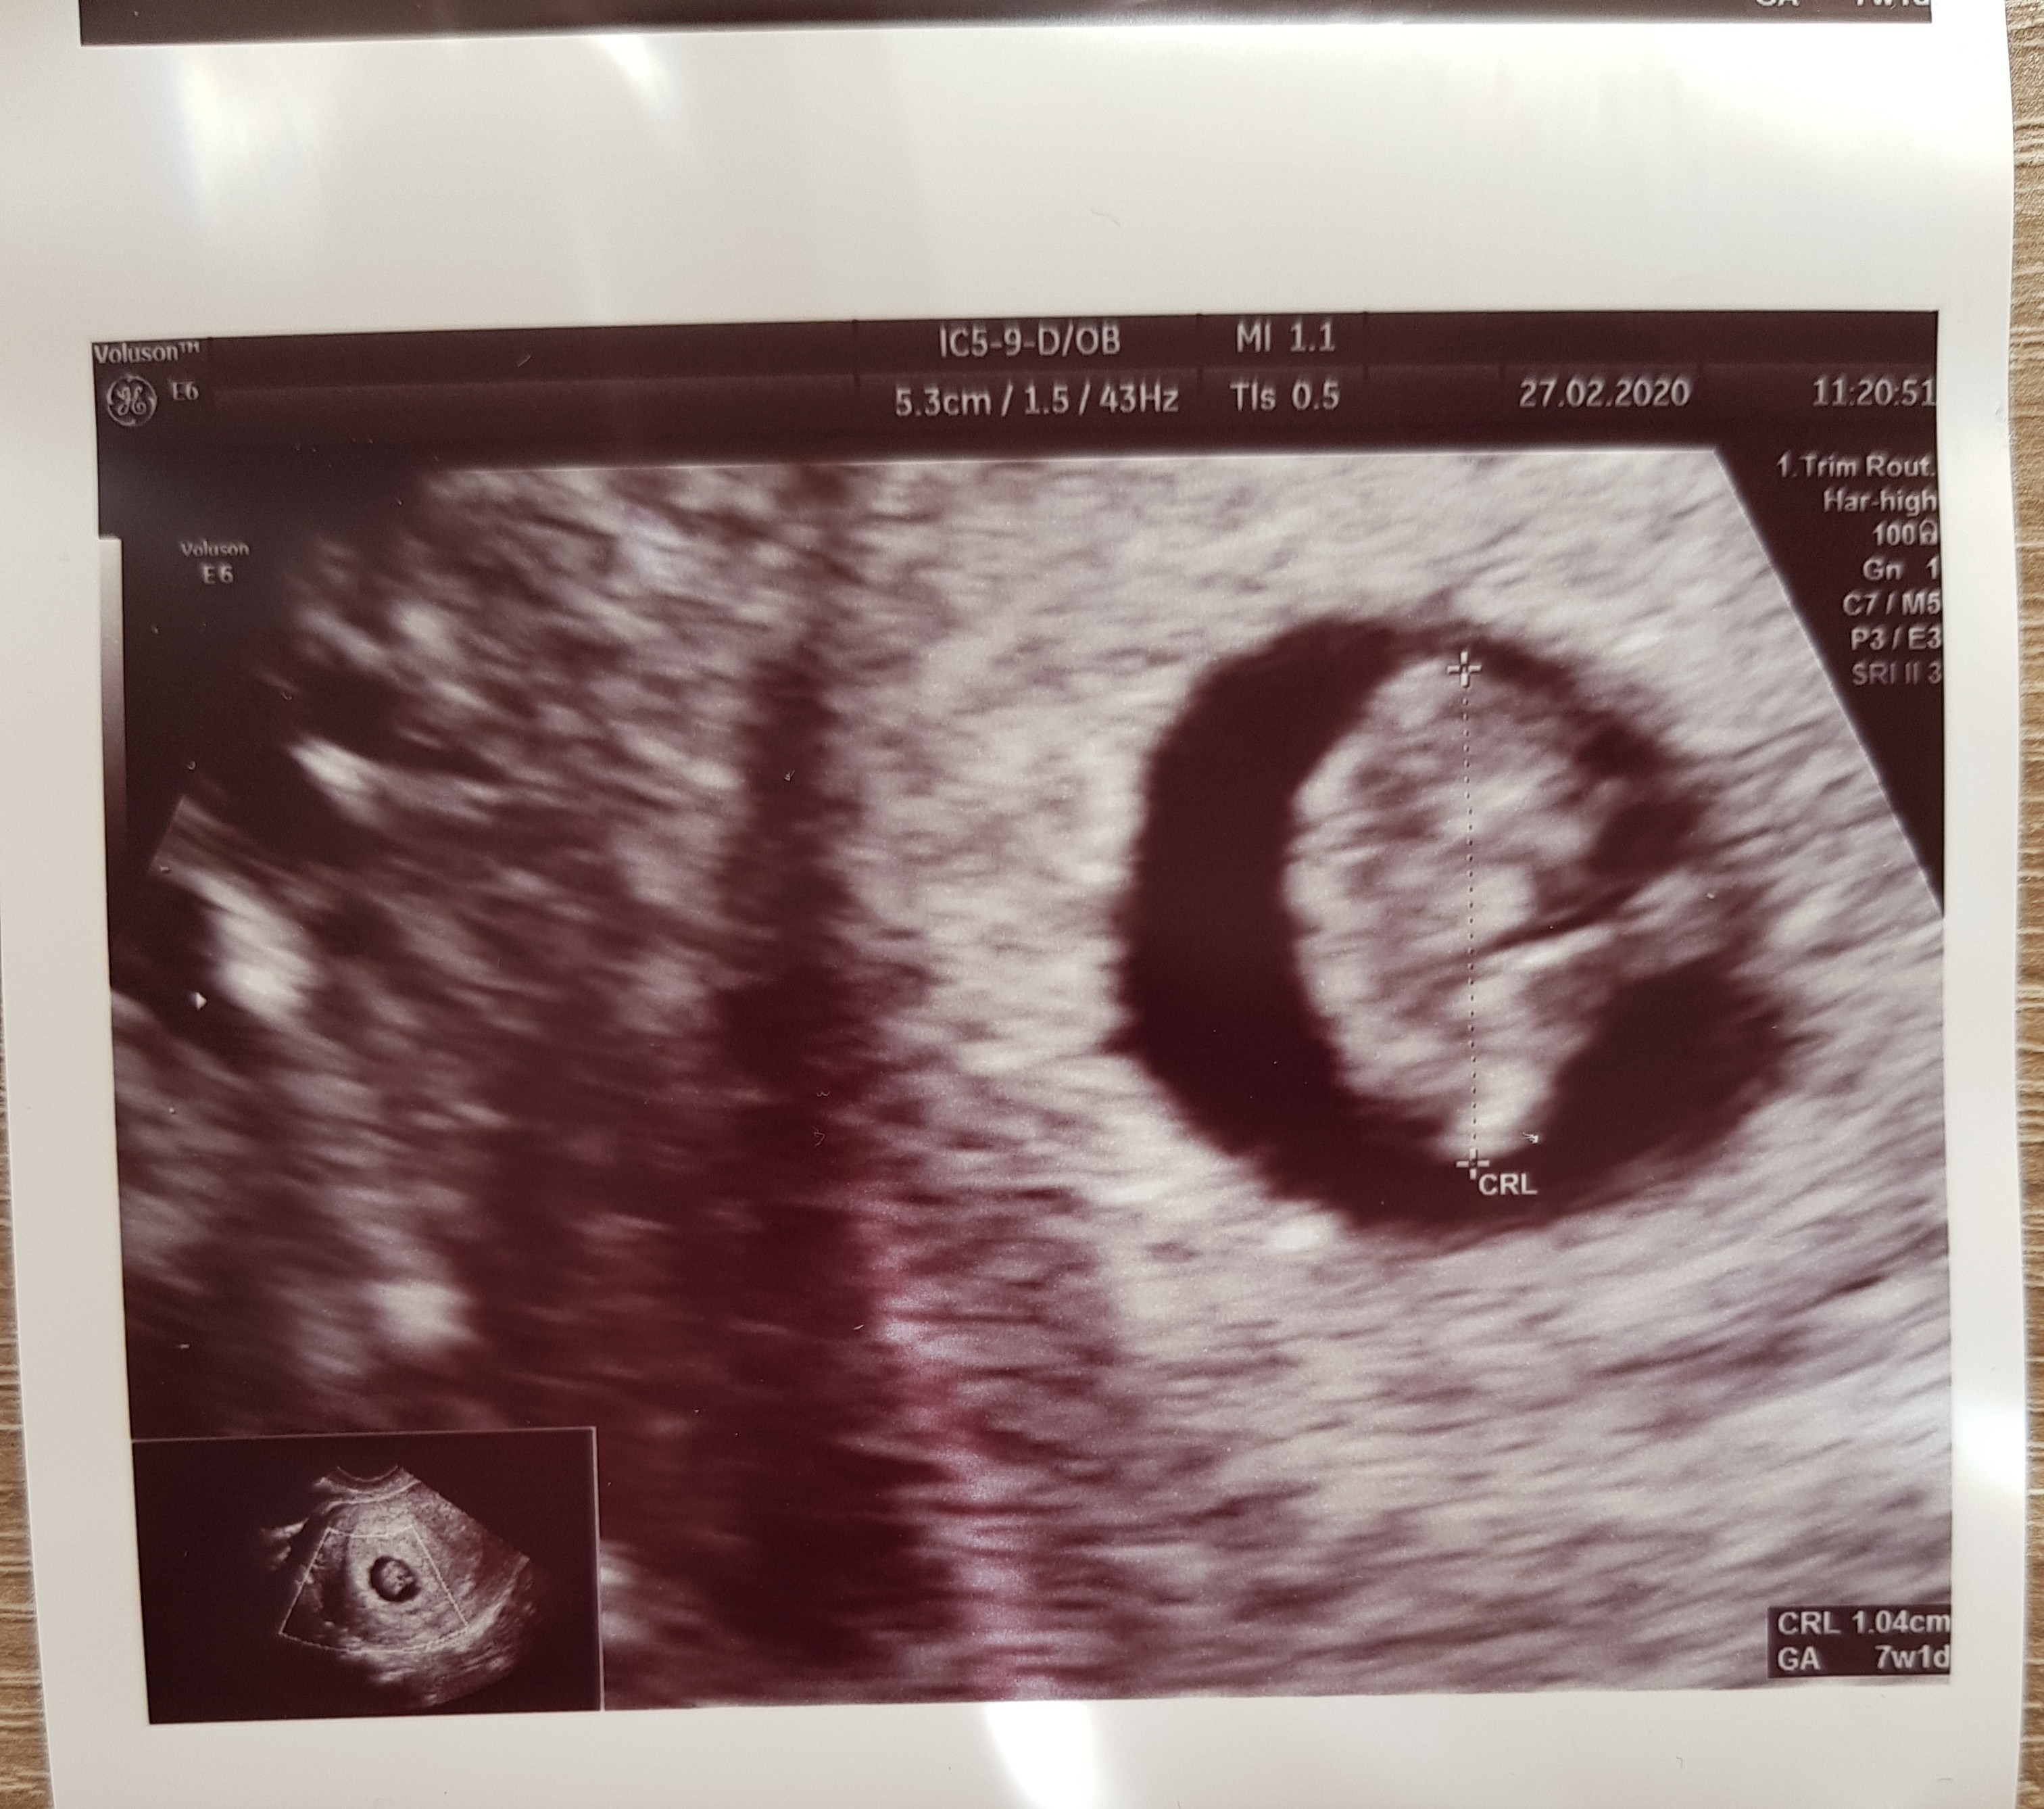

Jutro mam o 19 wizyte-trzymajcie kciuki za serduszko, bo bylabym juz spokojniejsza